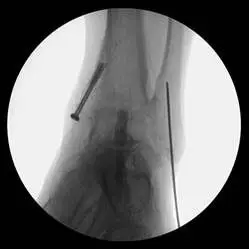

These are pics of the fusion prior to takedown

These first three pics are placement of screws in the medial malleolus and distal fibula to aid in stability.